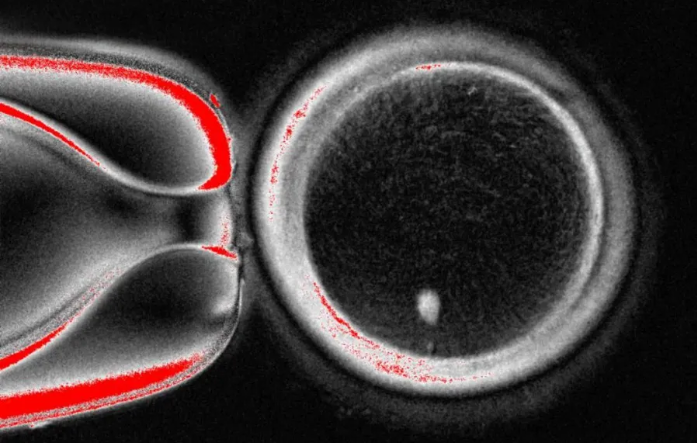

ორეგონის ჯანმრთელობისა და მეცნიერების უნივერსიტეტის კვლევითი ჯგუფის მიერ მიგნებული ახალი ტექნიკა კანის უჯრედიდან იღებს ბირთვს - რომელიც შეიცავს სხეულის ასლისთვის საჭირო მთელი გენეტიკური კოდის ასლს.

შემდეგ ეს კოდი თავსდება დონორის კვერცხუჯრედში, რომელსაც არ აქვს გენეტიკური მასალა.

ჯერჯერობით, ტექნიკა მსგავსია იმ ტექნიკისა, რომელიც გამოიყენეს ცხვრის, დოლის - მსოფლიოში პირველი კლონირებული ძუძუმწოვრის - შესაქმნელად, რომელიც 1996 წელს დაიბადა.

თუმცა, ასეთი კვერცხუჯრედი არ არის მზად სპერმატოზოიდით განაყოფიერებისთვის, რადგან ის უკვე შეიცავს ქრომოსომების სრულ კომპლექტს - 46 ქრომოსომას.

ზოგადად, მემკვიდრეობით ვიღებთ 23 ქრომოსომას თითოეული მშობლისგან, სულ 46-ს, ამ ექსპერიმენტულ კვერცხუჯრედს კი უკვე აქვს 46 ქრომოსმომა.

ამიტომ შემდეგი ეტაპია კვერცხუჯრედის დარწმუნება, რომ გადაყაროს ქრომოსომების ნახევარი და ამ პროცესს მკვლევარებმა „მიტომეიოზი“ უწოდეს (სიტყვა ნიშნავს მიტოზისა და მეიოზის შერწყმას, უჯრედების დაყოფის ორ გზას).

ჟურნალ Nature Communications-ში გამოქვეყნებულმა კვლევამ აჩვენა, რომ შეიქმნა 82 ფუნქციური კვერცხუჯრედი. ისინი განაყოფიერდა სპერმით და ზოგიერთი მათგანი ემბრიონის განვითარების ადრეულ ეტაპებზე გადავიდა. არცერთი არ განვითარდა ექვსდღიან ეტაპს მიღმა.